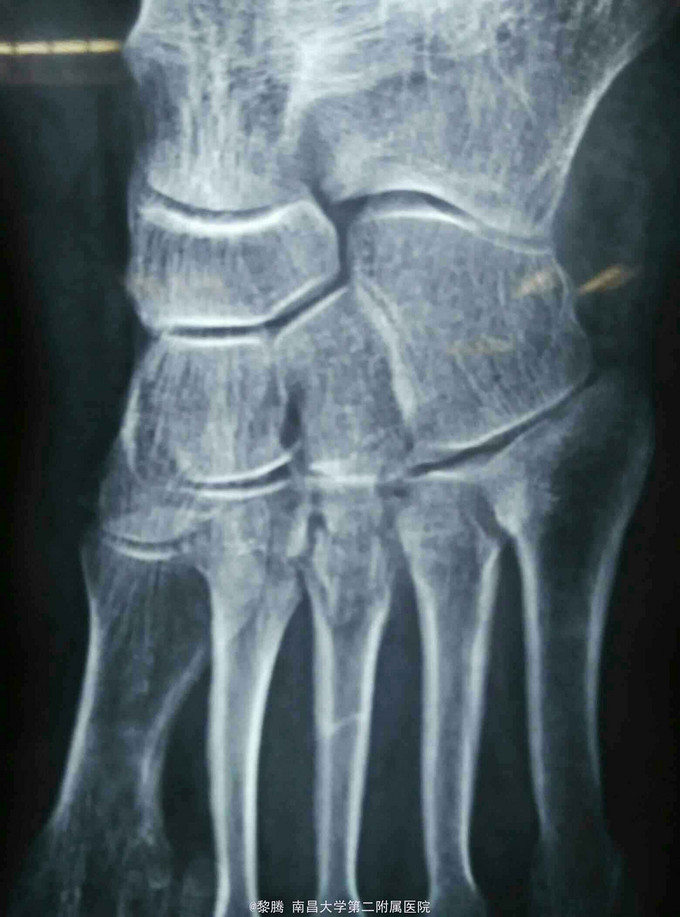

外伤致左足肿痛,活动受限6小时 患者老年女性,因外伤砸中左足,致左足出现明显肿痛,伤后当即出现左足活动受限,患者伤后急诊入我院就诊行左足正斜位片提示左侧跖骨骨折,随后收入住院进一步治疗。

查体:左足肿胀明显,局部皮肤可见明显青紫及张力性水泡,左足背动脉搏动存在,左足各趾感觉无明显异常,肢体末梢血运可 辅查:左足正斜位片提示左第3跖骨骨折。

诊断:左足第3跖骨骨折 治疗:骨折切开复位内固定